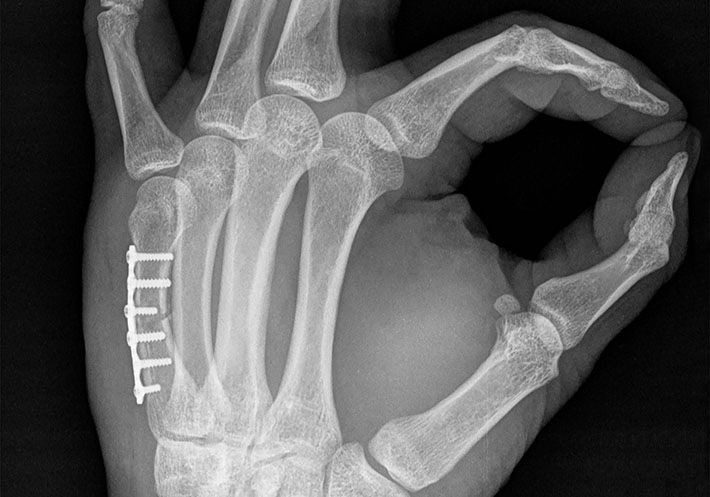

Las placas para huesos pequeños, según se detalla en este estándar, son placas metálicas que se utilizan para fijar extremidades distales en el cuerpo humano, como los dedos de las manos y de los pies; áreas del cráneo y la parte superior del rostro.

Según Joe Turner, miembro de ASTM, este estándar (F3437) proporciona métodos de prueba útiles para placas de un tamaño tan pequeño.

“Aunque existen estándares para las pruebas de las placas óseas metálicas, debido al tamaño más reducido de las placas que se utilizan en las extremidades distales, puede ser difícil preparar y ejecutar estas pruebas”, afirma Turner, gerente de ingeniería en Acuity Surgical. “Por consiguiente, este estándar ofrece métodos de prueba alternativos que son más apropiados para las placas utilizadas en la fijación de fracturas de huesos pequeños”.

El estándar ayudará a abordar el desempeño de estas placas óseas y proporcionará una base para su comparación mecánica.